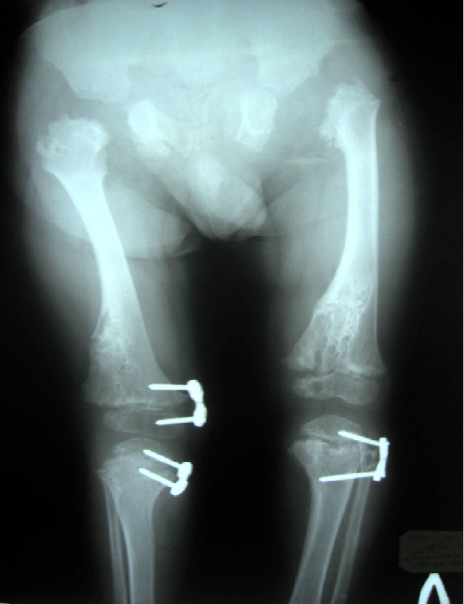

In order to guard against progression of the windswept deformity of the lower limbs, we decided to proceed by applying temporary hemiepiphysiodesis (plates were applied to the medial sides of the physes of right distal femur and right proximal tibia to correct the valgus deformity, with simultaneous application for the lateral aspect of the left proximal tibia to overcome the varus deformity) (Figure 6 [Fig. 6]).

Figure 6: Intraoperative radiographs of the knees. Plates for hemiepiphysiodesis applied to medial sides of the physes of right distal femur and right proximal tibia for correction of genu valgum and lateral aspect of left proximal tibia for correction of genu varum.

This technique might provide a guided growth of the long bones and has been used frequently in patients with skeletal dysplasia [8]. Ten months postoperative assessment revealed, satisfactory correction of 15º of genu valgum (left) and 5º of genu varum (right) was achieved.